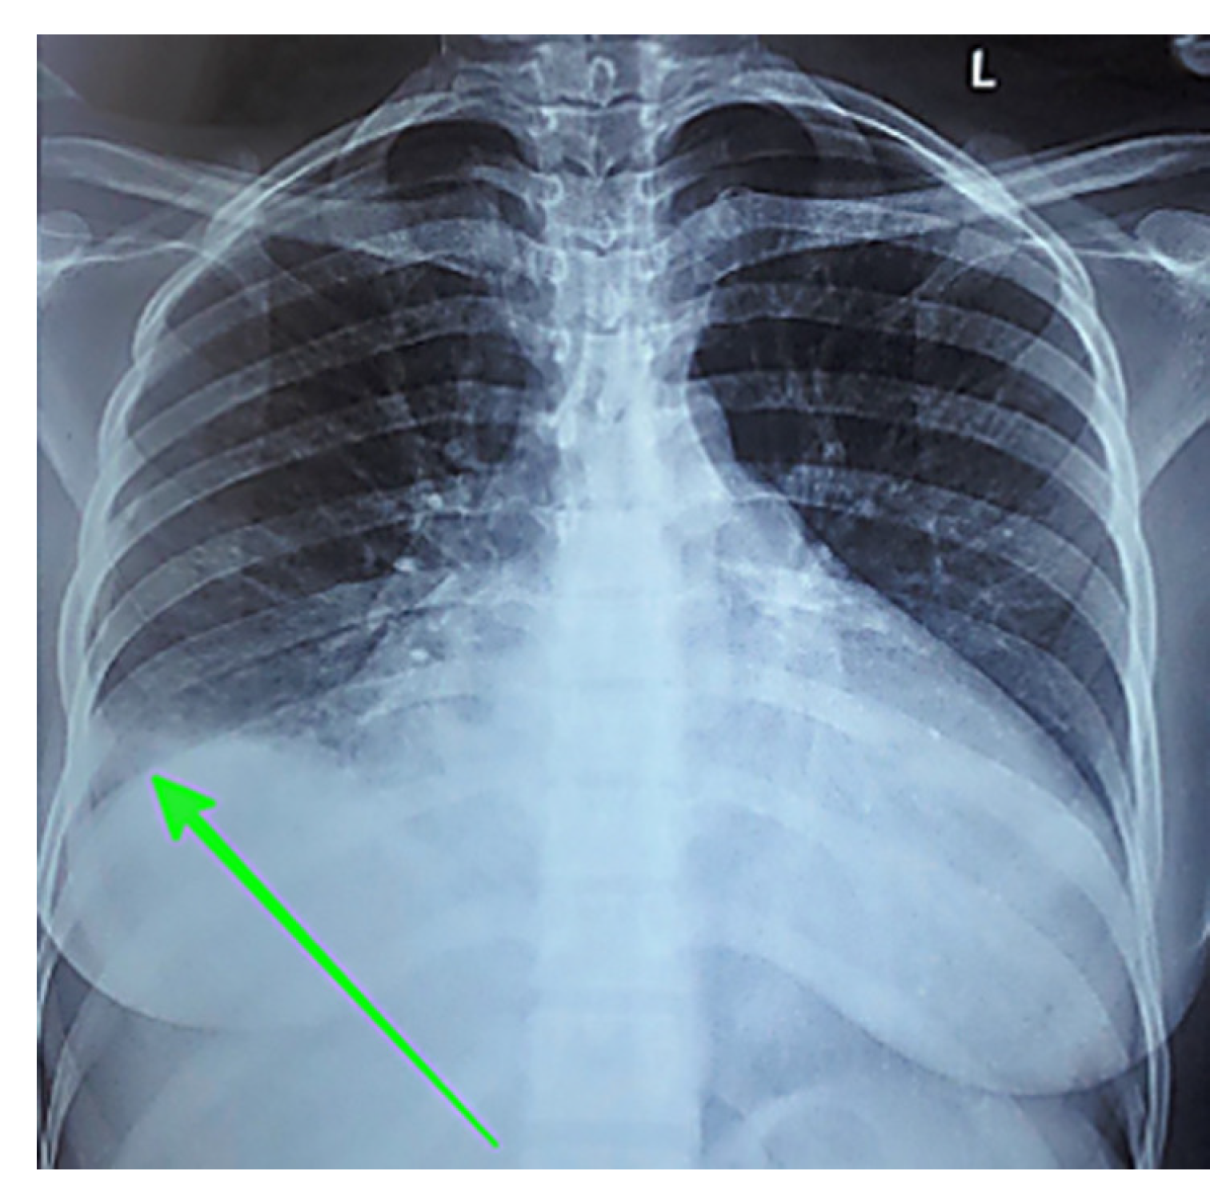

Two representative test cases from the dataset’s most prevalent modalities (i.e., CT scan and X-ray scan) demonstrate how model capabilities translate to real-world performance. The chest X-ray case (Figure 10) illustrates an example of the nature of model performance. Table 6 presents detailed component analysis for this example. LVLMs generally identified core components such as image modality, anatomical location, and pathological findings with high fidelity for simple cases [16]. However, multiple LVLMs also introduced the descriptor large, which was absent from the ground truth. Additionally, most models correctly identified laterality (right-sided) and reproduced visual markers (parenthetical arrow descriptions), though these elements aid clinical interpretation but are not represented as UMLS concepts. This pattern appeared in other test cases as well, indicating a tendency of these models to amplify the perceived prominence of findings. Among SVLMs, performance varied considerably. MoonDream2 retained most components accurately despite the simplified visual marker. In contrast, Qwen 2.5 failed entirely by misidentifying both modality (CT instead of X-ray) and anatomy (kidney instead of chest), despite having a greater parameter count than Qwen 2-VL and SmolVLM.